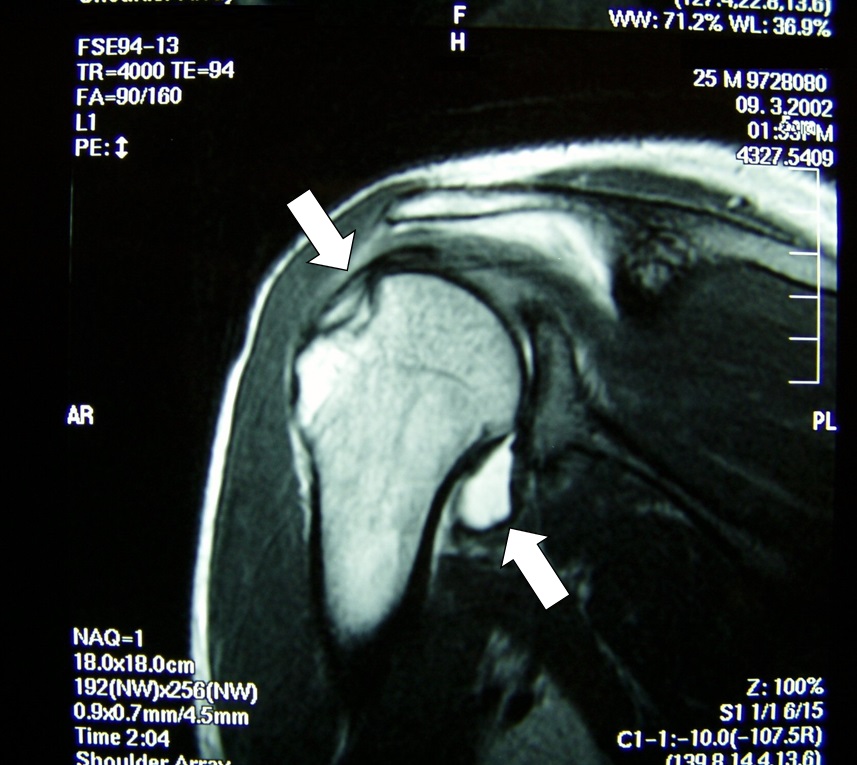

通過X射線、應力拍片檢查關節面的適宜性。最近通過CT、MRI檢查(照片2),可以很容易掌握軟骨組織的損傷程度。

照片2 整復後的MRI圖像。肱骨周圍由於出血顯示為高信號(白色)